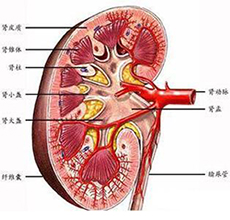

急性肾衰竭(ARF)

疾病介绍:急性肾衰竭(ARF)是指肾小球滤过功能在数小时至数周内迅速降低而引起的以水、电解质和酸碱平衡失调以及氮质代谢产物蓄积为主要特征的一组临床综合症,…【详细】